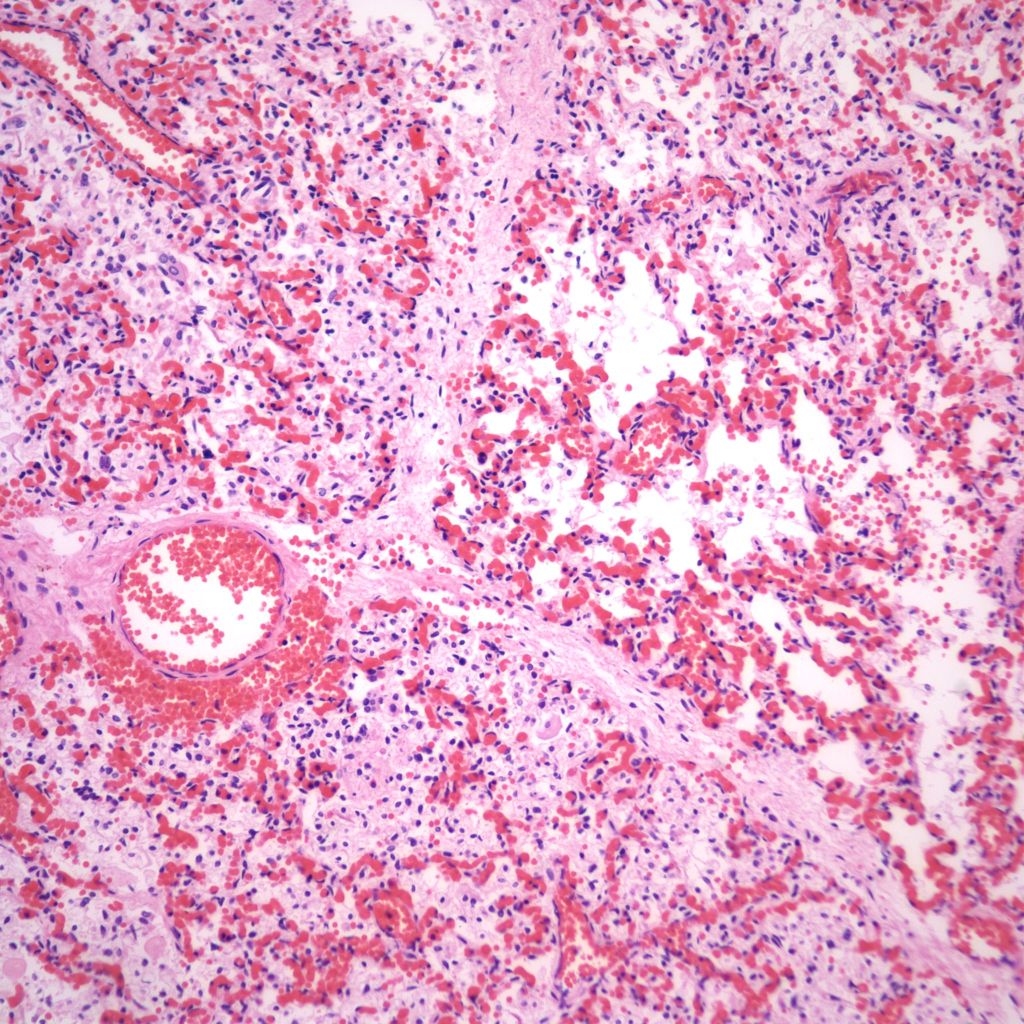

Hemorrhage and congestion:

Beside hemorrhage in the visceral pleura, there may be deeper connective tissue interstitial hemorrhage in the lung. The capillaries in other areas of the lung with pleural petechiae are often engorged as well, and the rigors of gasping and pressure change may account for deeper hemorrhages (Fig 20a, b).

Focal hemorrhages may also be found in the airways usually with evidence of hemorrhages in other organs suggestive of disseminated intravascular coagulation and shock (Fig 21).

The mechanism for many hemorrhages is obscure. With elevated left atrial pressure, for example with heart failure, but more acutely with closure of the ductus arteriosus, elevated atrial pressure would be reflected in dilatation of the pulmonary veins in the septa (Fig 22).

In turn this pressure should passively increase pulmonary capillary pressure. A similar increase in atrial pressure occurs with sudden acute twin transfusion prior to death (Fig 23).